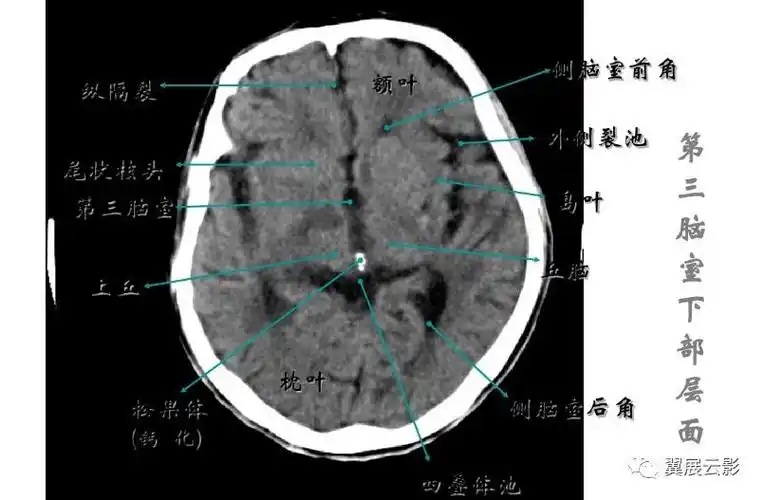

颅脑常见疾病ct诊断